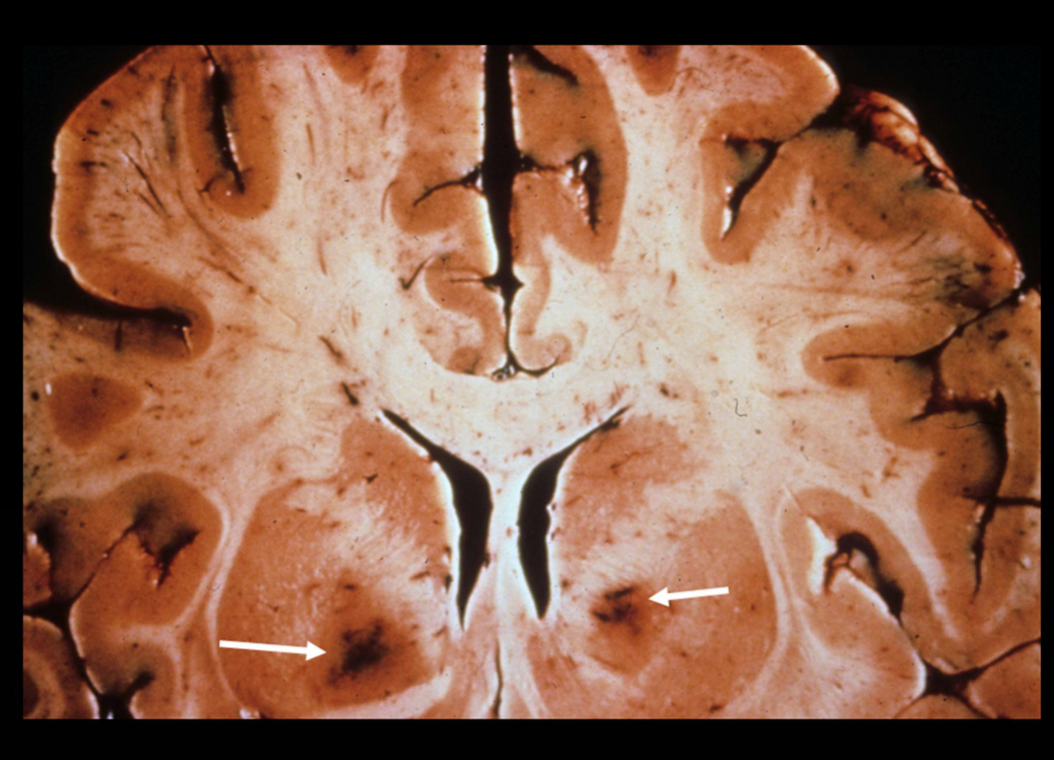

What pathology is shown in the provided image?

Cortical atrophy (consistent with Alzheimer disease)